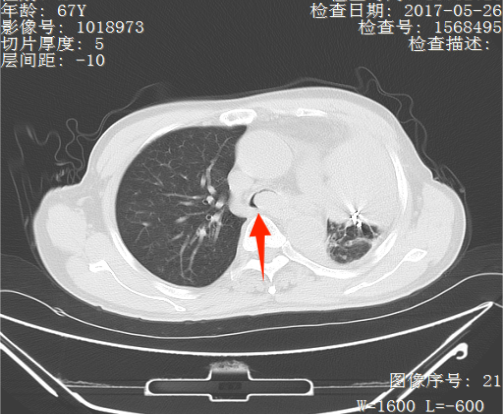

近年来,贵州航天医院各科室紧跟医学前沿,不断强技术、补短板,大力开展新技术、新项目,完成了许多高精尖、高难度、本地区“首例”的技术,填补了医院医疗技术空白,满足了群众日益增长的医疗需求。 贵州航天医院呼吸与危重症医学科是贵州省内呼吸疾病治疗规模最大,诊疗项目最全的呼吸疾病品牌科室,呼吸介入技术达到了全国先进水平,在贵州省内处于领先的地位。 本期,我们将为大家带来呼吸与危重症医学科特色技术——气道支架置入技术治疗呼吸不畅(已纳入乙类医保报销)。 案例分享 一患者因出现呼吸困难、气急等症状,听说我院呼吸与危重症医学科呼吸系统疾病诊疗实力在省内属于前列,慕名前来就诊,入院后,呼吸与危重症医学科为患者完善了胸部CT检查,提示:左主支气管肿瘤生长至气管下段,左肺不张,对此,科室立即组织多学科(MDT)讨论,对患者进行全面的诊断评估,诊断为:左肺鳞癌,左肺不张,气管下段内生型狭窄,左主支气管堵塞。 在充分了解患者及家属的治疗需求和征得治疗同意后,为进一步减轻患者呼吸困难症状,决定为患者实施气道支架置入技术,通过将支气管镜插入到气管中,使用气道球囊扩张器对狭窄的气道进行扩张,在病变部位置入支架扩张狭窄的支气管后,患者安全返回病房。 国产镍钛记忆合金支架植入步骤 术后,患者左主支气管通畅。 什么是气道支架置入技术 气道支架置入技术是一种用于治疗气道狭窄及气道相关性瘘等疾病重要的手段,尤其适用于因恶性肿瘤或其他原因导致的呼吸困难患者。是利用一种保持管腔完整性的人造装置——支架并应用支架置入器在X线透视或支气管镜直视下将支架置入气道保持气道通气功能的一种方法。 目前气道支架最常见的类型有可膨胀金属气道支架、硅酮支架及混合性支架等,以可膨胀金属支架为最常用。 气道支架置入技术原理 是将具有一定张力和弹力的支撑物(即气管支架)置入气道内,将狭窄或塌陷的气道撑开,从而维持气道通畅,或堵住破裂的瘘口。根据气管、支气管不同部位的解剖特点和病变情况,选择对应型号的支架,并通过气管镜的指引,在病灶位置植入合适的支架,也可根据气道的收缩性、不规则性和狭窄程度,进行适当调整。 气道支架置入技术优势 (一)快速缓解呼吸困难:支架置入能够迅速撑开狭窄或塌陷的气道,显著改善患者的呼吸困难症状。 (二)降低气道塌陷风险:对于某些肿瘤或炎症引起的气道狭窄,支架置入可以稳定气道结构,降低气道塌陷和窒息的风险。 (三)创伤小、恢复快:相较于传统手术,气道支架置入术具有微创的特点,患者术后恢复较快,痛苦较小。 气道支架可减轻或抵抗外部压力,扩大狭窄气道后,中央气道梗阻的症状和体征可立即减轻或消除,肺功能、运动能力及生活质量也得到改善。理想的气道支架应具备对气道壁物理性刺激小、置入后不移位、能阻止肿瘤或组织向支架内生长、不影响排痰、可以并容易回收等特点。 贵州航天医院 呼吸与危重症医学科专家团队 廖江荣 国务院政府特殊津贴专家 二级教授 主任医师 贵州航天医院副院长 国家级学术任职: 第二届中国医药教育协会介入微创专业委员会呼吸分会副主任委员 中国抗癌协会肿瘤微创治疗专业委员会常务委员 中国防痨协会结核病转化医学专业分会常务委员 第一届中国人体健康科技促进会呼吸介入专委会常务委员 中国医疗保健国际交流促进会结核病学分会第三届委员会常务委员 中国抗癌协会肿瘤微创治疗专业委员会粒子治疗学组第四届委员会委员 中华医学会结核临床专业委员会内镜介入委员 中华医学会放射学分会第十五届委员会介入学组呼吸系统介入专业委员会委员 北京健康促进会中青年专家委员会胸部疾病精准活检分委会副主任委员 中国医师协会介入医师分会第二届委员会肿瘤消融专业委员会委员 中国结核病防治综合质量控制专家指导委员会委员 亚洲冷冻治疗学会常务委员 世界内镜医师协会呼吸内镜协会常务理事 内镜临床诊疗质量评价专家委员会委员 “西部呼吸介入联盟”副理事长 专业擅长: 呼吸系统(肺)疑难病的诊断及危重病的抢救,呼吸系统(肺)感染性、疑难性疾病介入快速诊断(ROSE),尤其在肺癌、肺小结节早期诊断,肺癌微创综合靶向治疗,难治性、复治性、重症肺结核诊疗,硬质支气管下复杂性气道狭窄诊治,纤支镜介入治疗气道肿瘤、结核、气道狭窄(球囊扩张、支架植入、高频电刀、氩气刀、冷冻、灌洗、注药、微波消融),间质性肺疾病的诊疗上具有极高水平;带领团队勇于创新,在贵州省率先开展多项新技术、新疗法,如CT引导下及纤支镜下I125粒子植入及CT引导下微波、射频消融介入治疗肺癌等多项新技术,带动了贵州省肺部疾病的介入治疗水平提高。 蒋 婷 呼吸与危重症医学科 总负责人 副主任医师 专业擅长:从医20余年,在呼吸系统疾病、介入呼吸病学、肺部结核、肺部肿瘤等方面具有丰富的临床经验和专业技能,尤其是慢性阻塞性肺疾病、支气管扩张、肺结核、耐药肺结核、肺癌、胸腔积液等肺部疾病的诊治、微创介入、危重病患者抢救。 现任中国防痨协会人兽共患结核病专业分会委员,中国女医师协会第一届介入专业委员会委员,贵州省基层呼吸疾病防治联盟-间质性肺疾病联盟委员,贵州省防痨协会第七届理事会理事,贵州省中西医结合学会呼吸专业委员介入呼吸病学组委员,贵州省遵义市中医药学会中西医结合肺病(呼吸)分会副主任委员,贵州省遵义市中医药学会中医肿瘤专业委员会常委;发表论文数篇,参与并主持多项科研项目。 李桂凤 呼吸与危重症医学科 三病区 主任 副主任医师 专业擅长:从事呼吸系统疾病、结核病学、介入呼吸病学、肿瘤综合治疗、呼吸康复等临床工作20余年,擅长呼吸内科常见病、多发病及疑难重症危重病症的诊治,尤其对重症疑难结核及耐药结核病、介入治疗(肺)呼吸系统疾病、呼吸危重病抢救等方面具有较高诊疗水平。 中国防痨协会非结核病专业委员会委员,贵州省中西医结合学会第六届呼吸专业委员会委员,贵州省康复学会睡眠障碍康复专业委员会委员,遵义市呼吸内科医疗质量控制中心委员,遵义市落实民生实事结核病筛查阅片专家组成员;主持及参与实用新型专利3项。 周裕祥 呼吸与危重症医学科 四病区 主任 副主任医师 专业擅长:经皮肺介入、经血管介入诊疗技术。 贵州省中西医结合学会呼吸专业委员会介入呼吸病学组常务委员,中国医师协会呼吸医师分会介入呼吸病学工作委员会呼吸病血管介入学组委员,贵州省中西医结合学会呼吸学分会委员,遵义市医学会放射肿瘤治疗学分会委员,中国医药教育协会介入微创呼吸分会委员,北京健康促进会中青年专家委员会胸部疾病精准活检分委会委员;曾赴重庆医科大学RICU、珠海市人民医院介入科进修学习。 杨 芳 呼吸与危重症医学科 内镜中心 主任 副主任医师 专业擅长:从事临床工作约16年,对呼吸危重病的救治有独到的见解,尤其擅长呼吸系统疾病的介入诊疗,对呼吸内镜下的诊治及经皮肺穿刺诊疗技术具有丰富的临床经验。 亚洲冷冻治疗学会委员,中国医药教育协会介入微创呼吸分会委员,西南结核病医院联盟第二届委员会秘书/委员,贵州省中西医结合学会第六届呼吸科专业委员会委员,贵州省中西医结合学会呼吸专业委员会介入呼吸病学组秘书,贵州省中西医结合学会呼吸专业委员会基层康复学组副组长,贵州水利电力医学科学技术会高原医学分会委员,遵义市中医院学会中西医结合肺病(呼吸)分会秘书/常务委员,遵义市医学会肿瘤学分会(第二届)委员,遵义市医学会放射肿瘤治疗学分会第二届委员;主持及参与科研课题多项,参编著作《呼吸内镜操作技术规范》、《介入结核病学》,发表论文数篇。 贵州航天医院 呼吸与危重症医学科专家团队 贵州航天医院呼吸与危重症医学科以呼吸危重症和介入呼吸病学为强力推手,以肺部感染性疾病及肺癌、肺小结节的早期精准诊疗、慢性呼吸疾病康复治疗为特色,以人才团队建设为核心的科室发展模式,现已成为省内呼吸疾病治疗规模最大,诊疗项目最全的呼吸疾病品牌科室。是贵州省医学重点学科、临床医学重点专科建设单位,遵义市首批呼吸重点学科、重点专科建设单位。是国家卫健委能力建设和继续教育肿瘤微创介入建设中心、贵州省县级医院微创介入培训中心、遵义市呼吸疾病临床医学中心。是国家呼吸医疗质量控制与管理哨点医院、遵义市呼吸内科专业医疗质量控制中心。是中国医药教育协会介入微创呼吸分会呼吸介入技术培训中心单位;国家卫健委海医会呼吸分会ROSE专委会“诊断性介入肺脏病学快速现场评价”培训基地;中国肺癌防治联盟“贵州航天医院肺结节诊治”分中心,中国人体健康科技促进会呼吸介入技术培训基地,贵州省中西医结合会呼吸学分会呼吸介入专委会主委单位。 基本情况 平均每年开展气管镜诊疗约4000例,经皮肺穿刺介入诊疗近千例,开展的项目包括经支气管镜(软、硬)下冷冻、氩气刀、高频电刀、球囊扩张、支架置入、超声内镜诊疗等气道介入诊疗技术,经皮肺穿刺活检及肿瘤消融术(微波、冷冻)、ROSE技术、内科胸腔镜诊疗及经血管介入诊疗技术,且多项呼吸介入诊疗技术在省内处于领先水平。 诊疗范围 致力于呼吸系统感染性、疑难性疾病的介入快速精准诊疗;肺癌与肺小结节早期精准诊疗水平项目提升。擅长于呼吸系统(肺)疑难病的诊断及危重病的救治,尤其在肺癌、肺小结节的早期诊断;肺癌综合靶向治疗;肺结核综合诊疗;肺部疾病的介入诊疗在省内处于前沿水平。